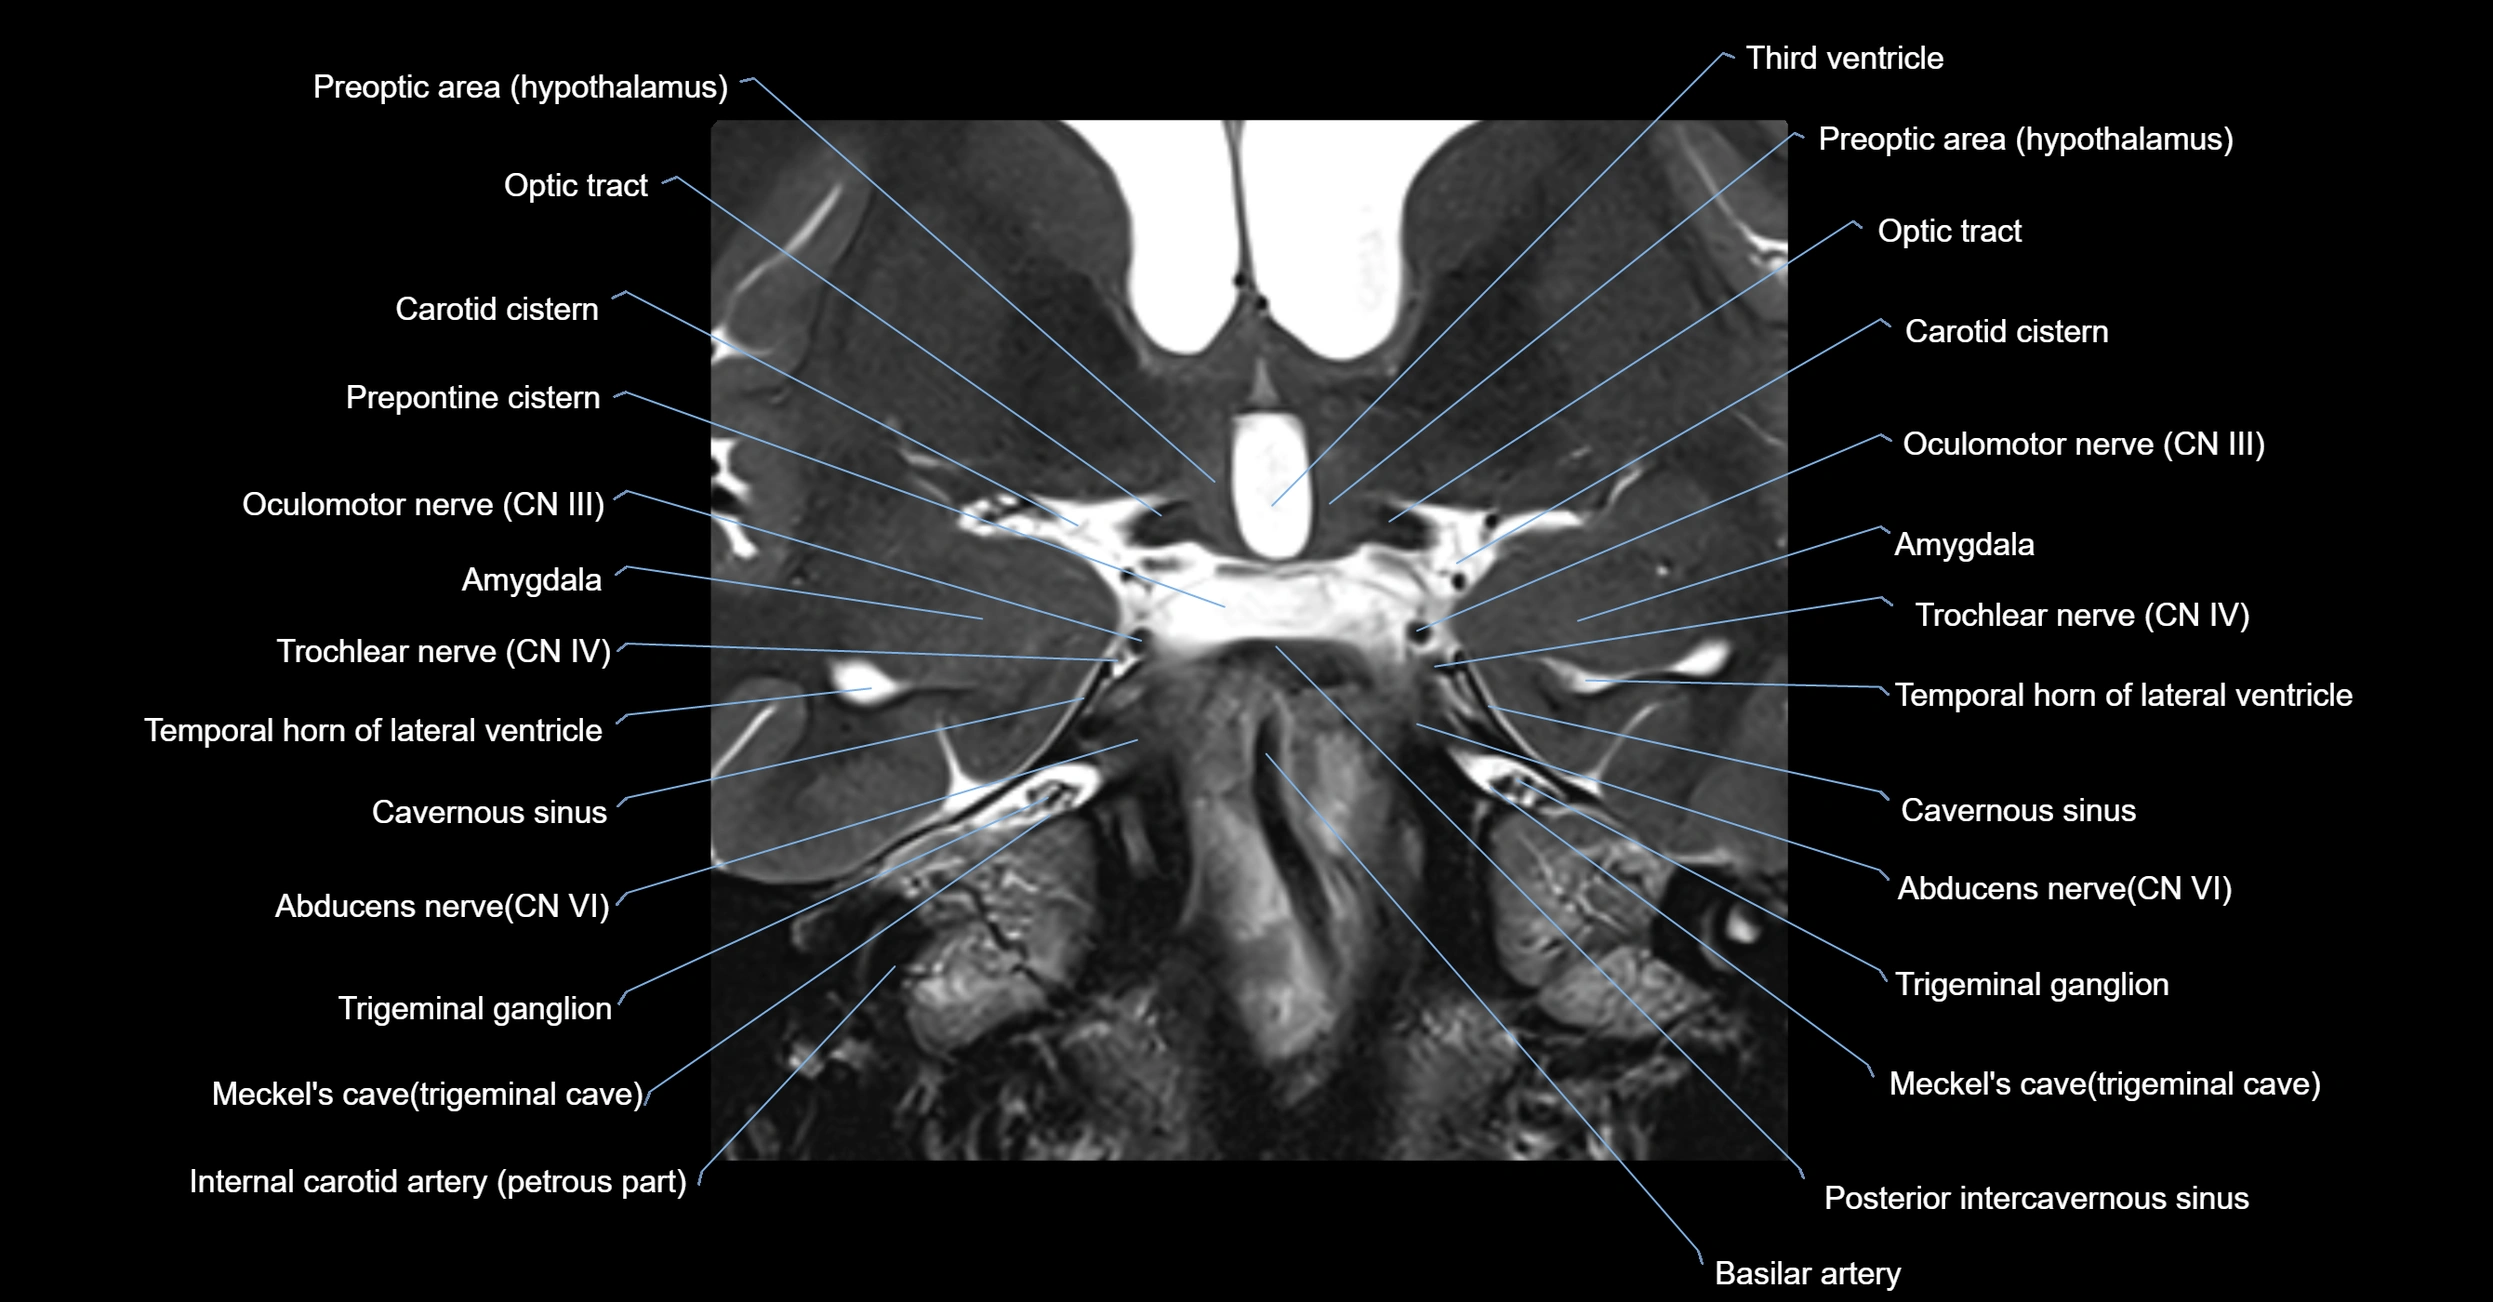

MRI Appearance

The abducens nerve is a small, thin, linear structure

Best visualized on high-resolution T2-weighted 3D MRI sequences (e.g., FIESTA or CISS)

Seen as a hypointense (dark) line running from the brainstem at the pontomedullary junction, traversing the prepontine cistern, and entering Dorello’s canal under the petrosphenoidal ligament, then into the cavernous sinus, and finally the orbit

May be challenging to visualize in standard MRI due to its small size

Pathology may be inferred by absence, displacement, or enhancement of the nerve

MRI images